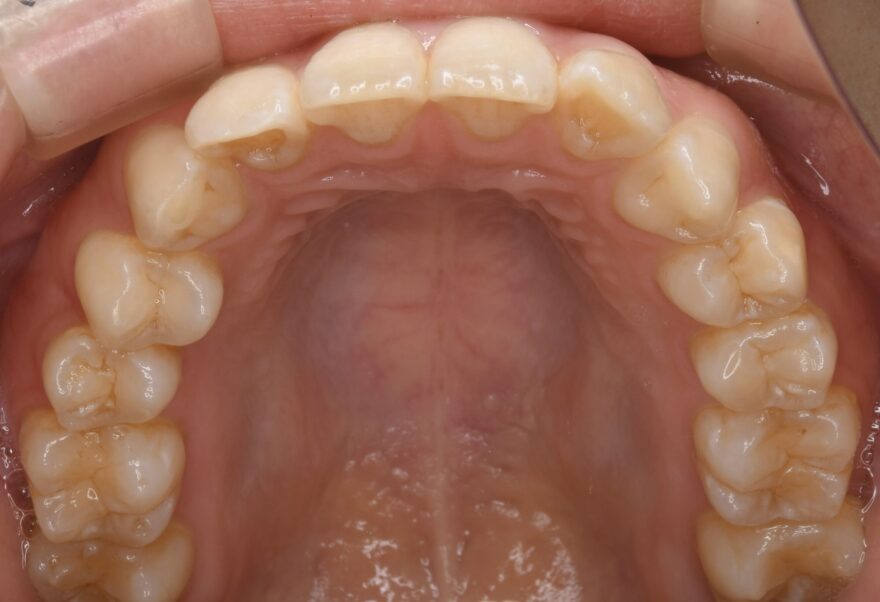

初診時の口腔内写真

前歯のガタガタが気になります。

治療後の口腔内写真

約2年の治療期間で、ここまで美しい歯並びになりました。

前歯も綺麗に並びました。

インプラントの上部構造は仮歯からセラミック歯へと交換しています。

下顎の前歯にはワイヤーによる保定装置を装着しました。